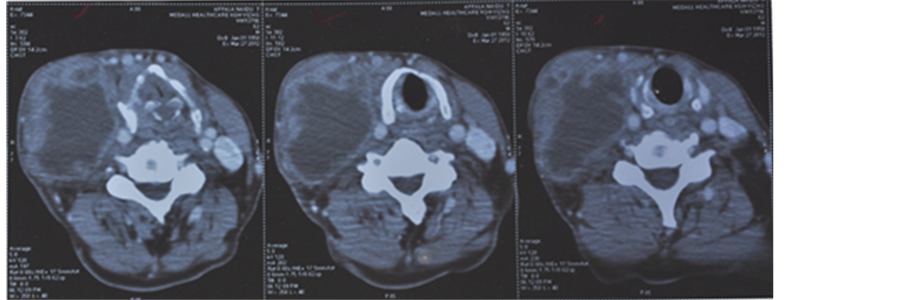

A 54-year-old gentleman, with a history of at least 20 pack years cigarette smoking, presented with progressive dysphagia and swelling in right side of neck of 2 months duration. On evaluation, there was a right level III cervical lymph node measuring 5 cm × 4 cm. Nasopharyngolaryngoscopy showed a growth 4 cm × 3 cm involving the right aryepiglottic fold, extending on to thevallecula. Biopsy from the growth was reported as squamous cell carcinoma. The patient was started on weekly cisplatin 40 mg/m2 and nimotuzumab 200 mg with radiation therapy. He received 3D conformal radiotherapy on linear accelerator with a daily dose of 200 cGy, 5 days/wk to a total dose of 6600 cGy/33 fractions and 6 cycles of chemo-immunotherapy. On completion of treatment, there was appreciable reduction in the size of the lymph node but it was still clinically palpable having a mean size of 1 cm × 1.5 cm. A PET was done to evaluate the functional uptake in the cervical lymph node. PET CT revealed mild uptake in the cervical lymph node. To address the residual disease in neck, functional neck dissection was done and histopathology of the dissected nodes showed no viable tumor deposits, suggesting a complete pathological response.

The patient was followed up for 24 months; CT scan displayed a good response to combination of radiation with cisplatin and nimotuzumab (Figure 1).

21st Feb 2011 5th July 2011

Figure 1. (a) Pretreatment―CECT of neck showing right upper cervical lymph node measuring 5 cm × 4 cm with central necrosis; (b) Post treatment―CECT of neck showing very minimal enhancing lesion in the right side of neck. Post CT & RT, the residual disease measures 1 cm × 0.7 cm.